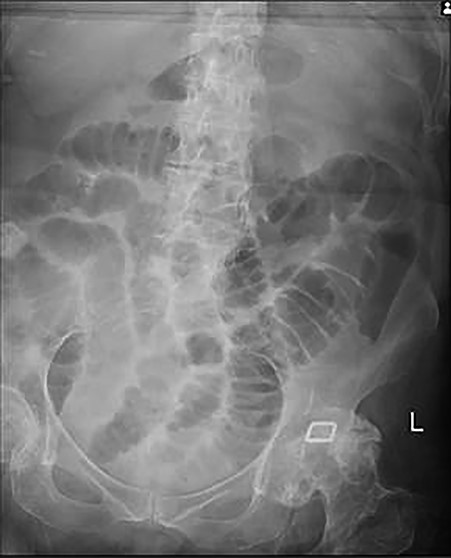

Plain abdominal X-ray demonstrated a calcified lesion on the right as well as distended loops of small bowel (Fig. 1). Abdomino-pelvic contrast CT scan showed an abnormal gallbladder containing pockets of air and a fistulation through the lateral part of D2,with a 22 mm calcified lesion within the ascending colon (Fig. 2a–d). Based on the history, physical examination and CT scan findings, our diagnosis was of resolving gallstone ileus.

a,b,c,d: CT images scout, axial, coronal and sagittal planes, respectively demonstrating gallstone as well as distended loops of small bowel.